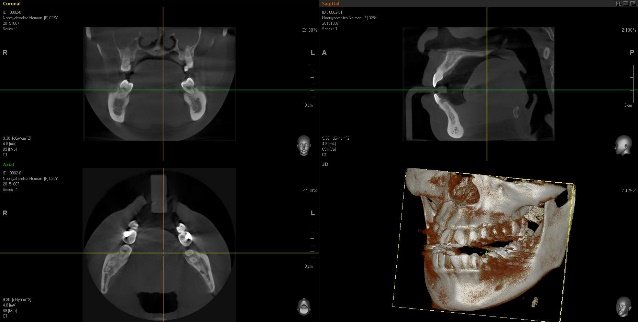

Diagnostic Imaging Technologies

| Technology | Companies | Benefits | Limitations | Approximate Cost |

MRI ![]() | GE Healthcare, Siemens Healthineers, Philips Healthcare | Gold standard for disc position assessment; visualizes soft tissues; no radiation | Expensive; time-consuming; contraindicated with certain implants | $800-$1,500 per exam |

CBCT ![]() | Planmeca, KaVo, Carestream Dental, Dentsply Sirona | Excellent bone detail; lower radiation than CT; can detect osseous changes | Limited soft tissue visualization; cannot directly visualize disc | $250-$500 per exam |